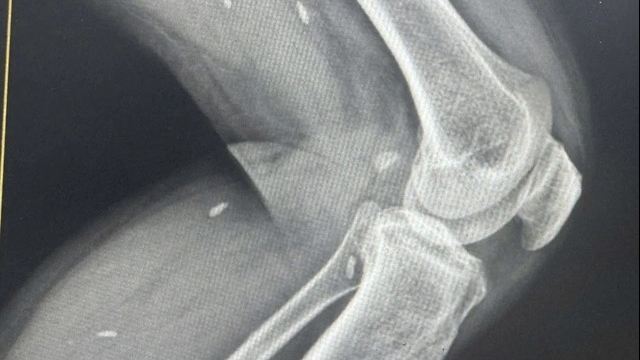

Trước đó, một phụ nữ 49 tuổi, sau khi phẫu thuật mí mắt ở Viện thẩm mỹ ARIES đã bị sưng bầm mắt phải, chảy máu không cầm được, tụ máu ở hốc mắt phải nhập Bệnh viện Mắt TP HCM cấp cứu. Tại đây, mắt phải bệnh nhân thị lực chỉ còn 1/10, mắt trái thị lực 8/10 và bầm nhẹ.

Các bác sĩ phẫu thuật giải áp hốc mắt, lấy máu tụ và dẫn lưu hốc mắt. Sau mổ, mắt phải của bệnh nhân tăng được thị lực lên 8/10. Bệnh nhân cho biết, trước đó đã phẫu thuật mí mắt tại Viện thẩm mỹ Aries. Bệnh viện Mắt báo cáo ca tai biến này cho Sở Y tế TP HCM. Ngay sau đó, Thanh tra Sở Y tế phối hợp Công an (PC06) và các lực lượng chức năng kiểm tra đột xuất cơ sở thẩm mỹ nói trên.